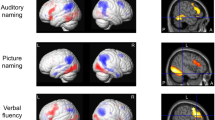

fMRI results—main effects

During auditory naming, main activations across all subjects were seen in the left posterior inferior temporal gyrus, bilateral parahippocampal gyrus, left inferior frontal gyrus, left cuneus/precuneus and supramarginal gyrus, left middle and inferior occipital gyrus, and left cerebellum (Fig. 1, online resource 4). During picture naming, main activations were seen in the bilateral fusiform gyrus, bilateral middle occipital gyrus, and right cerebellum.

Main fMRI activation during auditory naming and picture naming across all participants shown superimposed on sagittal and coronal slices at p < 0.05, corrected for multiple comparisons (FWE). Crosshairs indicate activation maxima in the left inferior temporal gyrus (auditory naming) and left fusiform gyrus (picture naming)